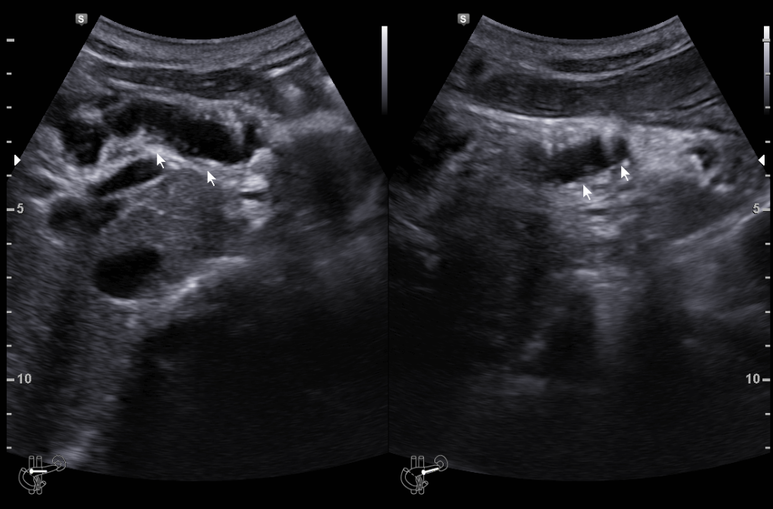

상기 환자 초음파 시행

체부 췌도가 13 mm까지 확장

미부도 확장 확인

췌두부의 췌도 확장과 결절 소견

IPMN, main duct type, 췌관내 유두상 점액 종양, 주췌관형으로 MRCP/ERCP등 검사 후 수술적 치료 상의 위해 의뢰함.